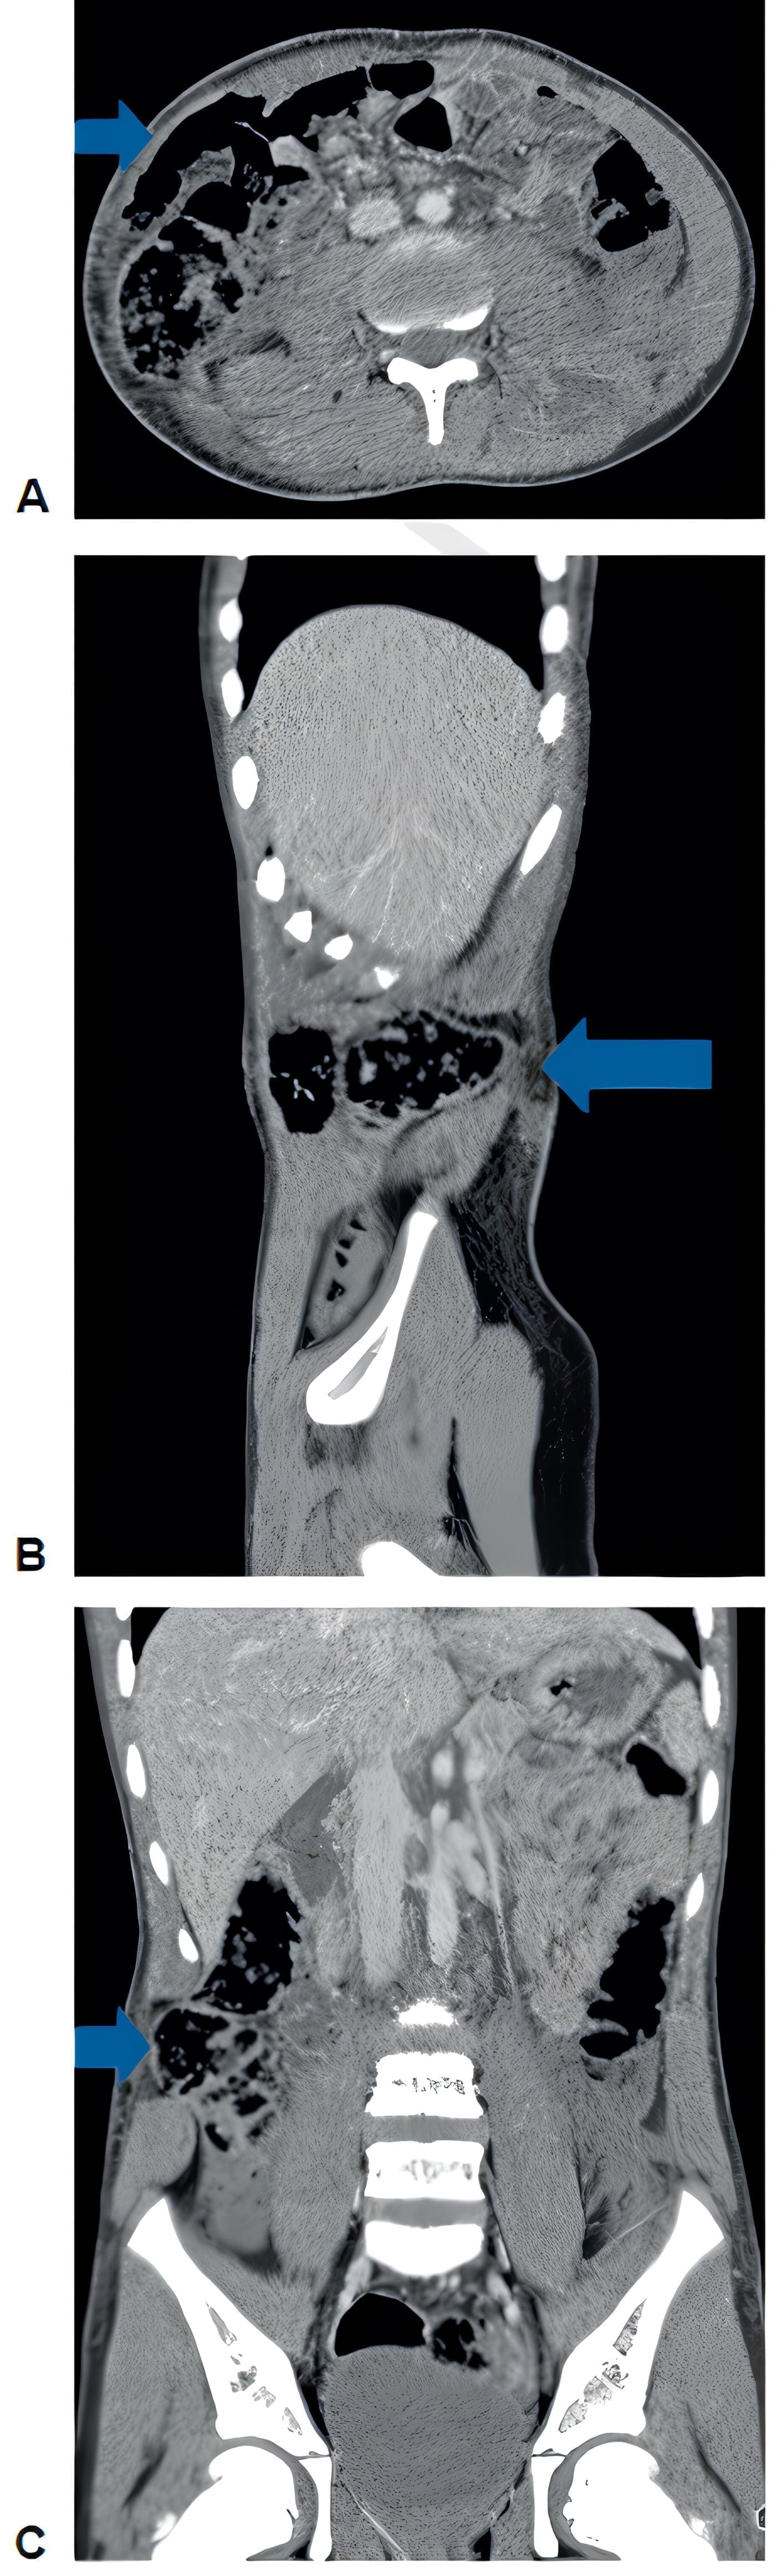

Dado el mecanismo del trauma, se llevó urgente a TC de abdomen, donde se apreciaron hernias traumáticas de la pared abdominal anterolateral y posterior, asociadas a laceración hepática adyacente al ligamento falciforme y escaso líquido libre en cavidad (Figura 3), además de una fractura corporal de T12 no desplazada y fractura de elementos posteriores de L3 desplazada, con canal medular conservado.

Figura 3. Tomografía de abdominal que muestra las hernias traumáticas de la pared abdominal.

A, corte axial, B, sagital y C, coronal. Las flechas indican la localización de la hernia traumática.

Fuente: servicio de radiología del hospital Pablo Tobón Uribe, Medellín, Colombia.

Se programó para cirugía y se realizó herniorrafía videoasistida con cierre primario y sin material protésico, sin complicaciones.

En cirugía se identificaron las hernias traumáticas de la pared, una anterolateral derecha con un defecto de 5 cm con ruptura del músculo recto, del oblicuo mayor, del menor y del trasverso hasta la región lateral, y otra hernia del retroperitoneo ipsilateral, que contenía asa de intestino delgado y salida de grasa perirrenal.